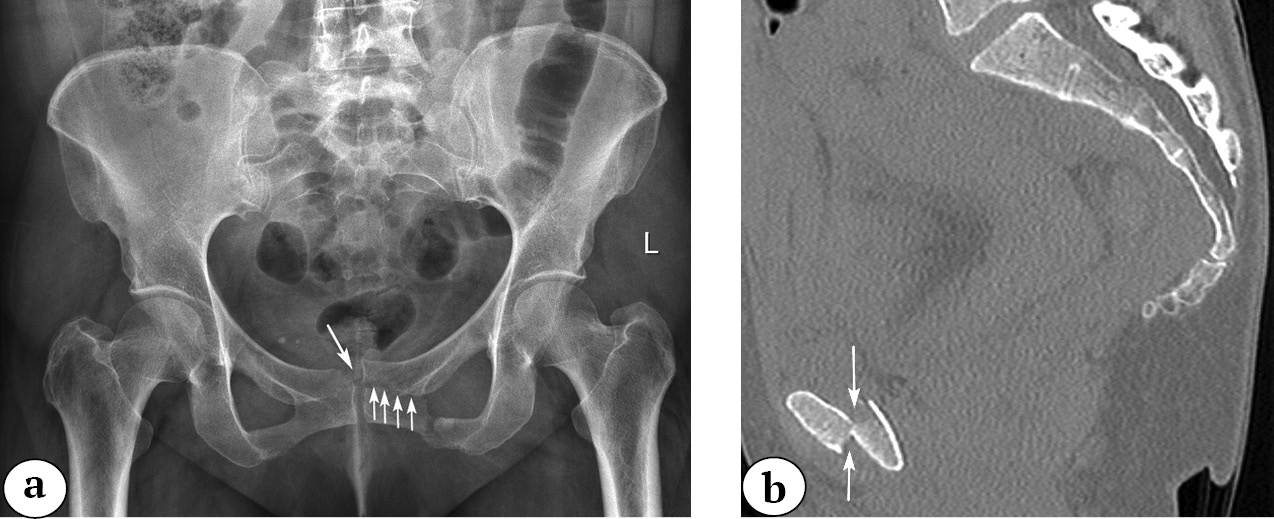

The drawback of such an approach is the absence of a commonly accepted Russian equivalent for the term “crescent fracture,” and it doesn’t take into account the degree of displacement of the fragments (subluxation, dislocation). In such situations, we suggest using the phrase “fracture-subluxation” or “dislocation of the ilium base” and specifying the degree of displacement of the ilium base fragment. For example, if there is a fracture with a displacement of less than 1 cm in the sacroiliac joint area, the injury can be described as a “fracture-subluxation of the ilium base” of type II (according to A. Day’s classification) (Fig. 8).

Fig. 8. 3D-CT image reconstruction of the pelvis, the inlet view. The arrows indicate the opening of the SIJ gap less than 1 cm

In another case, when there is a fracture with a displacement of more than 1 cm in the sacroiliac joint area, the injury can be described as a “fracture-dislocation of the ilium base” type II according to A. Day’s classification (Fig. 9).

Fig. 9. 3D-CT image reconstruction of the pelvis in the inlet view (a); 2D-CT image reconstruction of the pelvis in the axial view. Displacement of the fragments in the SIJ is greater than 1 cm. The arrow shows the level of the fracture of the iliac base in relation to the CPS, type II according to A. Day ( b)

However, when analyzing fractures in the area of the ilium base, we have encountered fractures that do not fit into existing classifications. For example, fractures that run along the entire base of the ilium without penetrating the sacroiliac joint. For such fractures, we propose our own term — “longitudinal fracture of the ilium base” (Fig. 10).

Fig. 10. Longitudinal fracture of the base of the iliac bone: a — 2D-CT image reconstruction in the axial view; b –3D-CT image reconstruction in the posterior view